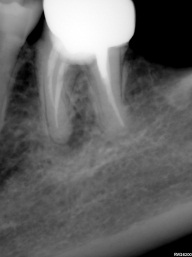

Perfurações dentarias são complicações no tratamento de canal que na maioria dos casos resulta em um prognóstico desfavorável, pois permite a entrada de microrganismos nos tecidos que envolvem o dente. Em alguns casos, devido ao seu difícil diagnóstico, acesso limitado, tempo decorrido ou tamanho da perfuração resultará em um desafio para o profissional conseguir um selamento adequado da área, sendo muito importante o conhecimento sobre o material que será empregado.